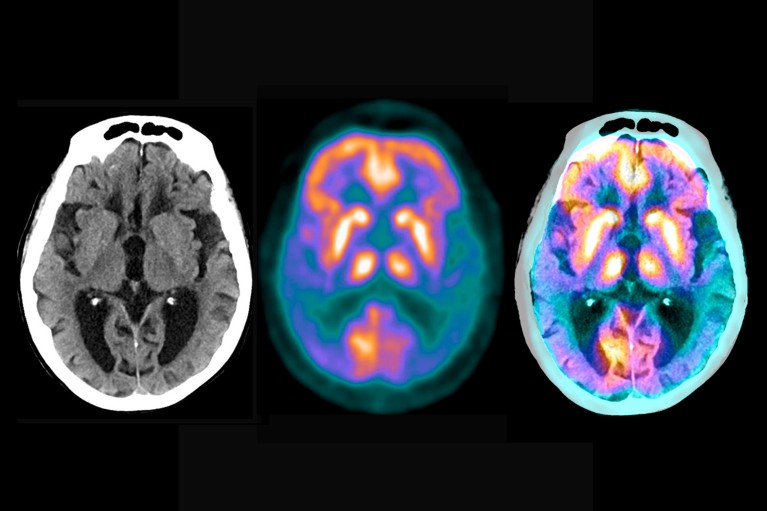

Brain scans reveal the extent of the damage caused by Alzheimer's disease

Key to the trial is a series of sensitive new biomarkers - measurements of the brain or blood that can read the state of the disease. Brain scans monitored the presence and severity of amyloid plaques and tau tangles; Blood or cerebrospinal fluid tests measure many other molecules in the pathological chain, such as different forms of amyloid and tau proteins. The researchers expect that the wealth of molecular and clinical data they generate will help reveal more about the mechanisms of Alzheimer's disease. "Current evidence points to tau as the initiator of Alzheimer's disease symptoms, disability and eventual death," Boxer said. "But this hypothesis needs to be tested in humans."